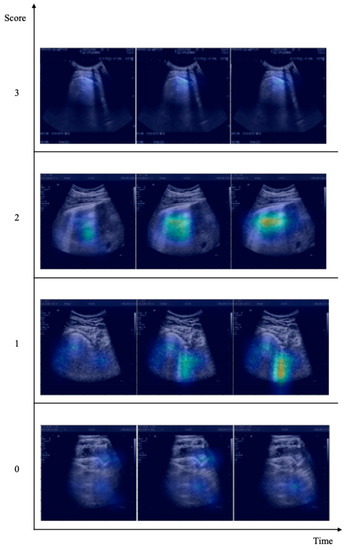

We used Grad-CAM to validate the network’s decision-making. The physicians evaluated whether the X3D correctly identified B-lines, pleural line abnormalities, or other patterns examined in the LUS scoring section, which is the procedure doctors use to assess patients’ health. Figure 3 shows the behavior of X3D in the most complex four-way classification task. We present the Grad-CAM results starting from the lowest score, indicating that the subject being considered is healthy, and approaching the highest score, indicating that the patient requires urgent respiratory assistance. The architecture accurately and thoroughly highlights all patterns, including A and B lines and small or large consolidations.

Figure 3. X3D network Grad-CAM results. The numbers on the vertical axis indicate the score associate to each video, while on the time axis three significant video frames are shown. The Grad-CAM activation map is superimposed to each frame, highlighting the image regions which are important for the classification.